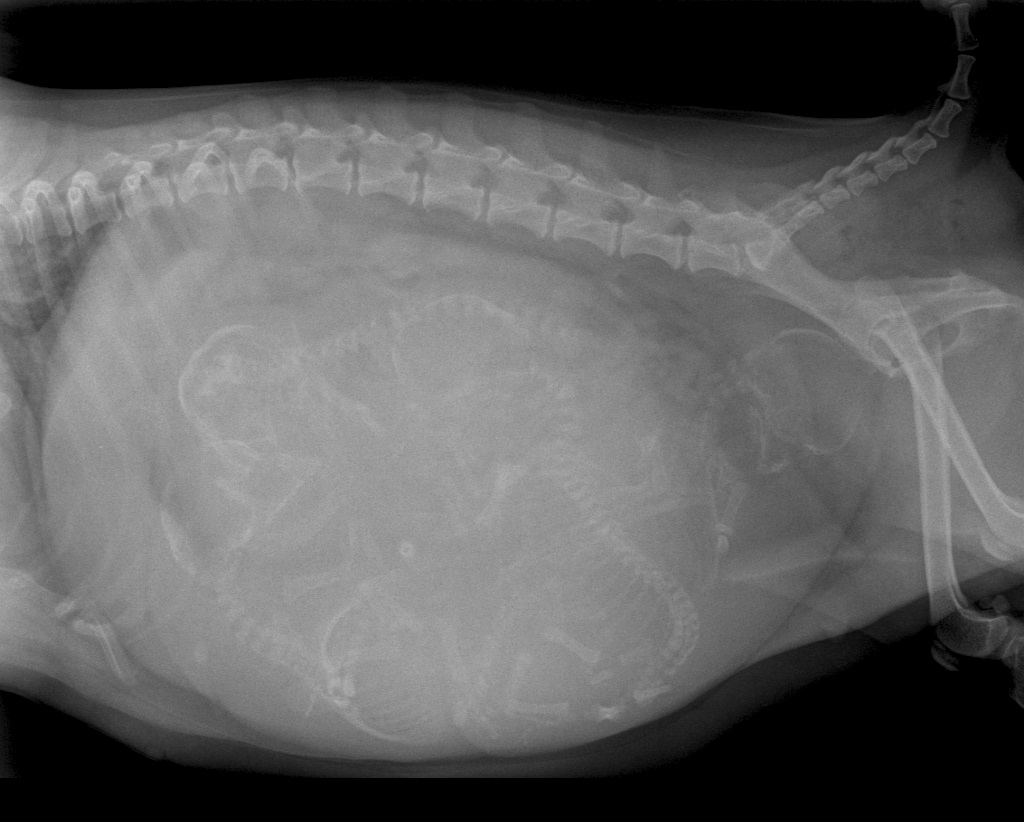

De bevalling stagneerde en het was voor ons zaak om snel te bepalen wat daar de oorzaak van was. Weeënzwakte? Of lag er een pup verkeerd? Of was de pup gewoon te groot voor het geboortekanaal? Omdat we weten dat chihuahua-pups nogal eens een te groot hoofdje hebben voor het bekken van de moeder besloten we direct een röntgenfoto van Luna's buik te maken. Op deze foto was goed te zien dat er inderdaad een pup met een fors koppie voor de bekkeningang vastliep en besloten we direct een keizersnede uit te voeren. Er werden vier mooie pups geboren, drie teefjes en een reu. Inmiddels zijn we anderhalve week verder en doen moeder en pups het fantastisch!

Röntgenfoto van Luna's buik: zoek de vier kopjes